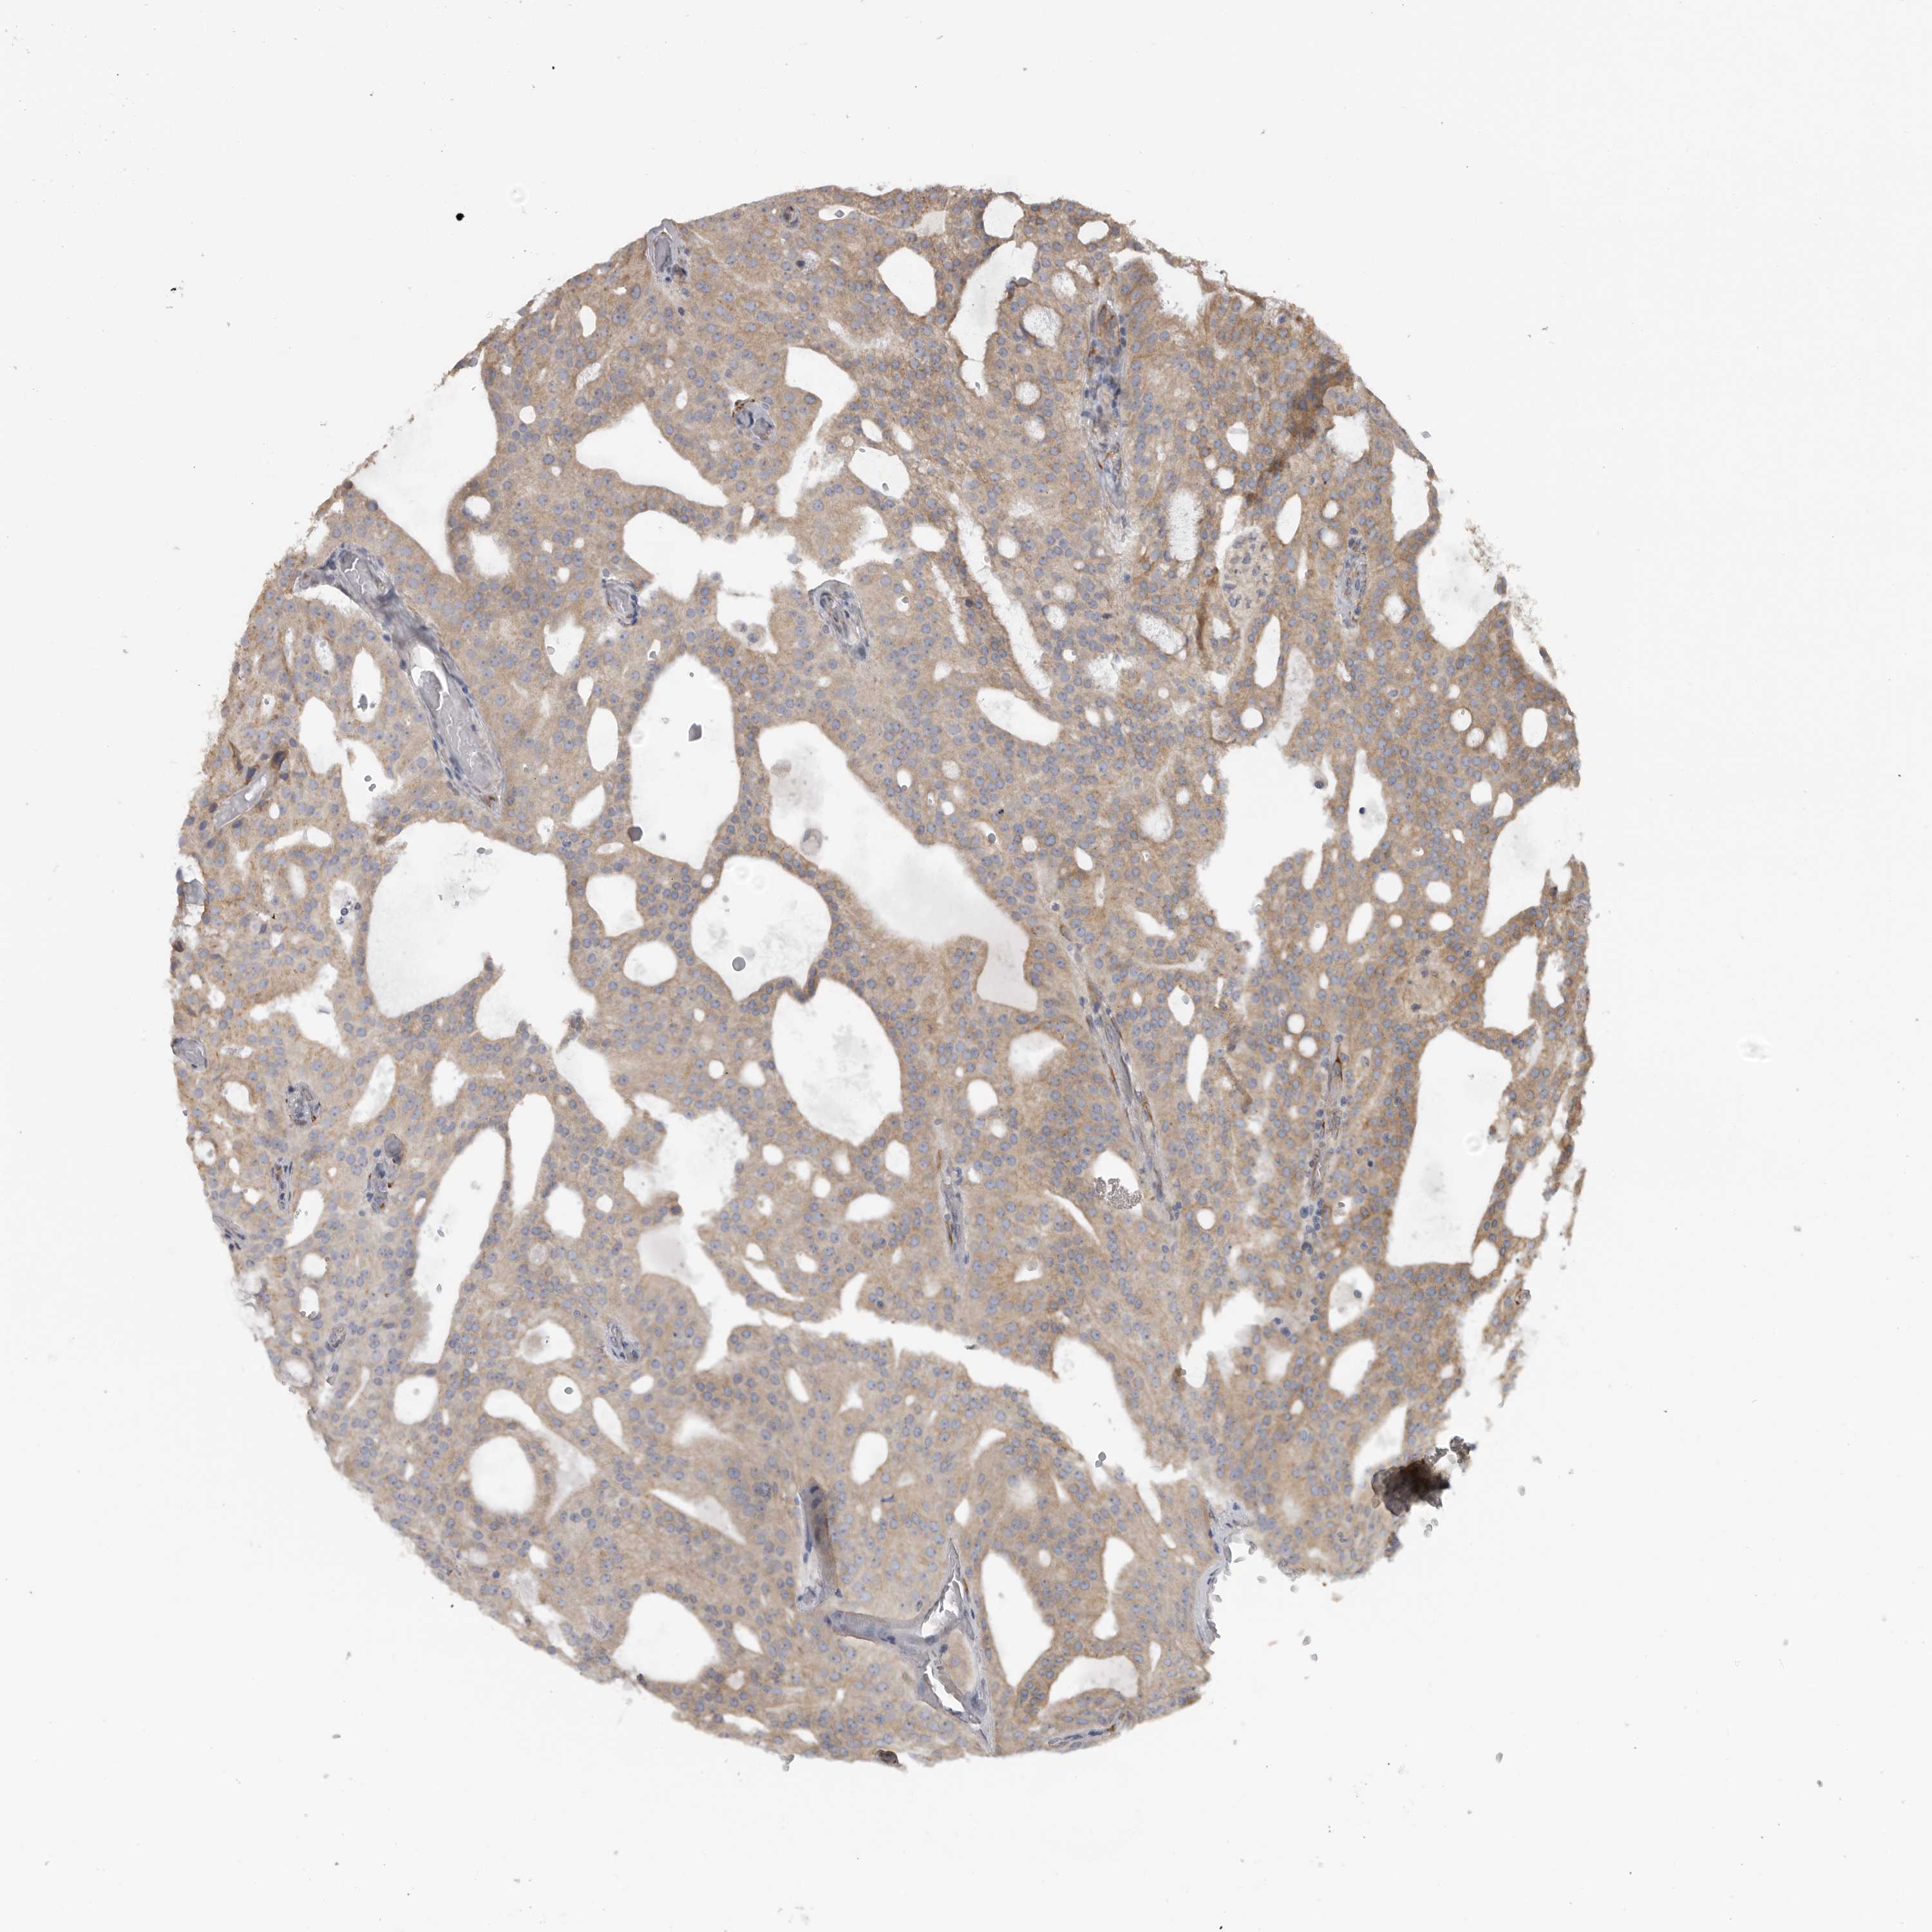

PROSTATE CANCER - Protein expressioni

A mouse-over function shows sample information and annotation data. Click on an image to view it in a full screen mode. Samples can be filtered based on level of antibody staining by selecting one or several of the following categories: high, medium, low and not detected. The assay and annotation is described here.

Note that samples used for immunohistochemistry by the Human Protein Atlas do not correspond to samples in the TCGA dataset.

Antibody stainingi

Antibody staining in the annotated cell types in the current human tissue is reported as not detected, low, medium, or high, based on conventional immunohistochemistry profiling in selected tissues. This score is based on the combination of the staining intensity and fraction of stained cells.

Each image is clickable and will lead to virtual microscopy that enables deeper exploration of all samples and also displays staining intensity scores, fraction scores and subcellular localization as well as patient and tissue information for each sample.

Antibody HPA028355

Antibody HPA028357

Staining

High

Medium

Low

Not detected

Intensity

Strong

Moderate

Weak

Negative

Quantity

>75%

75%-25%

<25%

None

Location

Nuclear

Cytoplasmic/membranous

Cytoplasmic/membranous,nuclear

Adenocarcinoma, High grade

Adenocarcinoma, Low grade

Adenocarcinoma, Medium grade